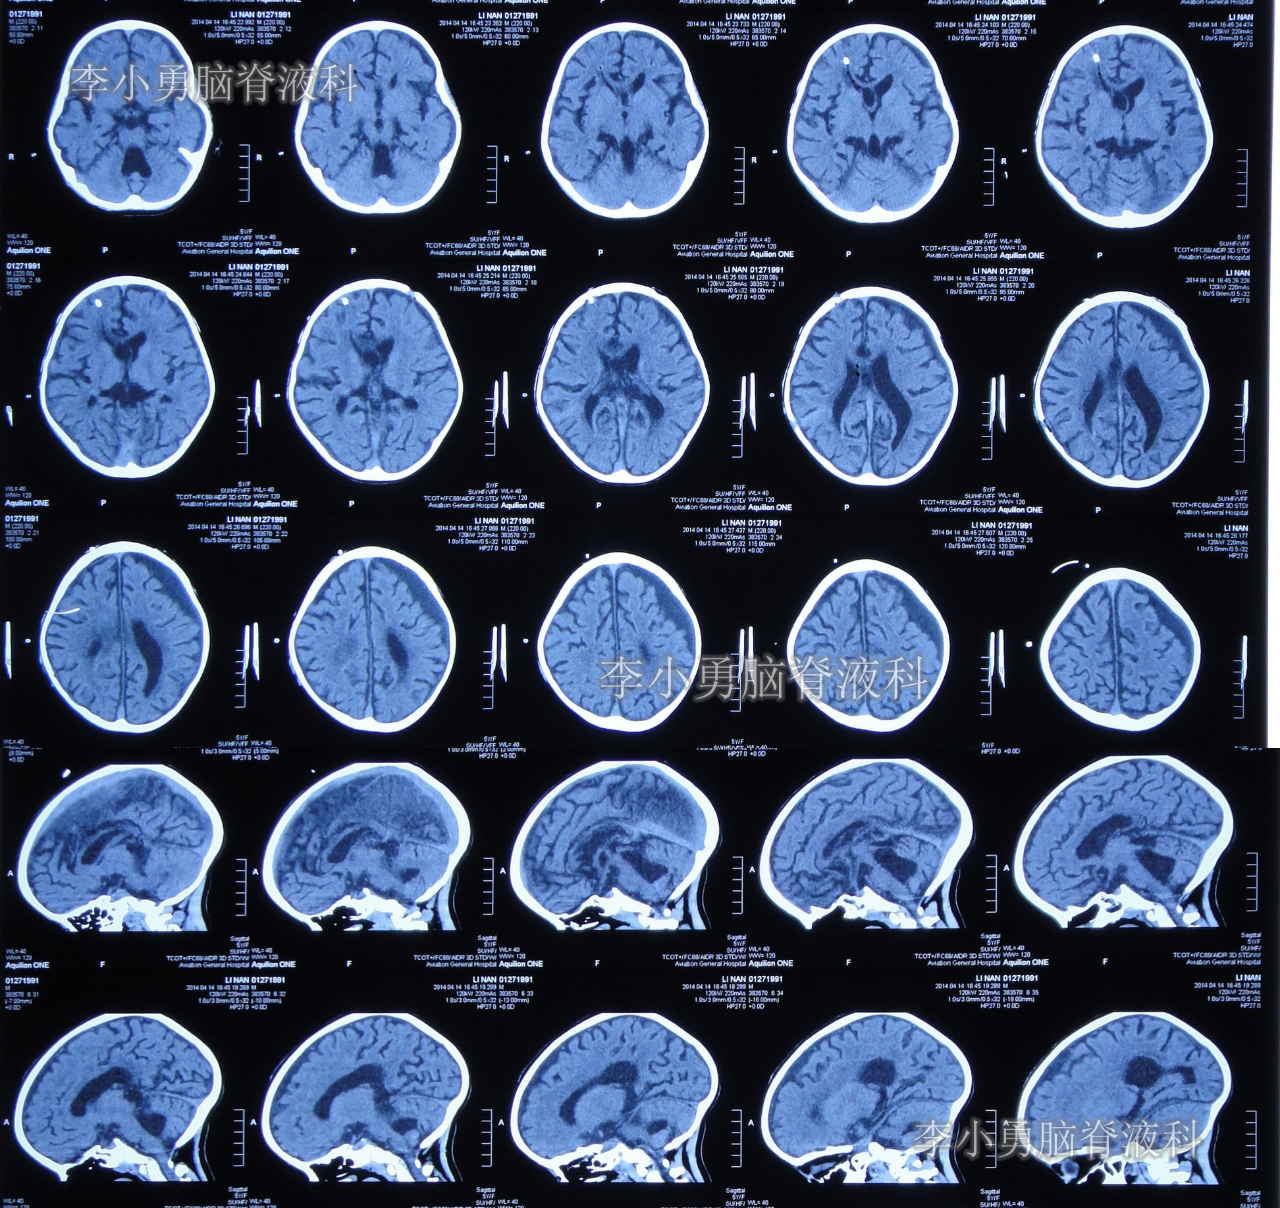

住院治疗第28天即2014年4月14日,复查头颅CT示幕上脑室大小恢复到基本正常的状态,第四脑室再度显著缩小但仍稍大(图-11)。

图-11:2014年4月14日头颅CT

住院治疗第30天即2014年4月16日,查头颅CT示幕上和第四脑室均基本正常(图-13)。

图-13:2014年4月16日